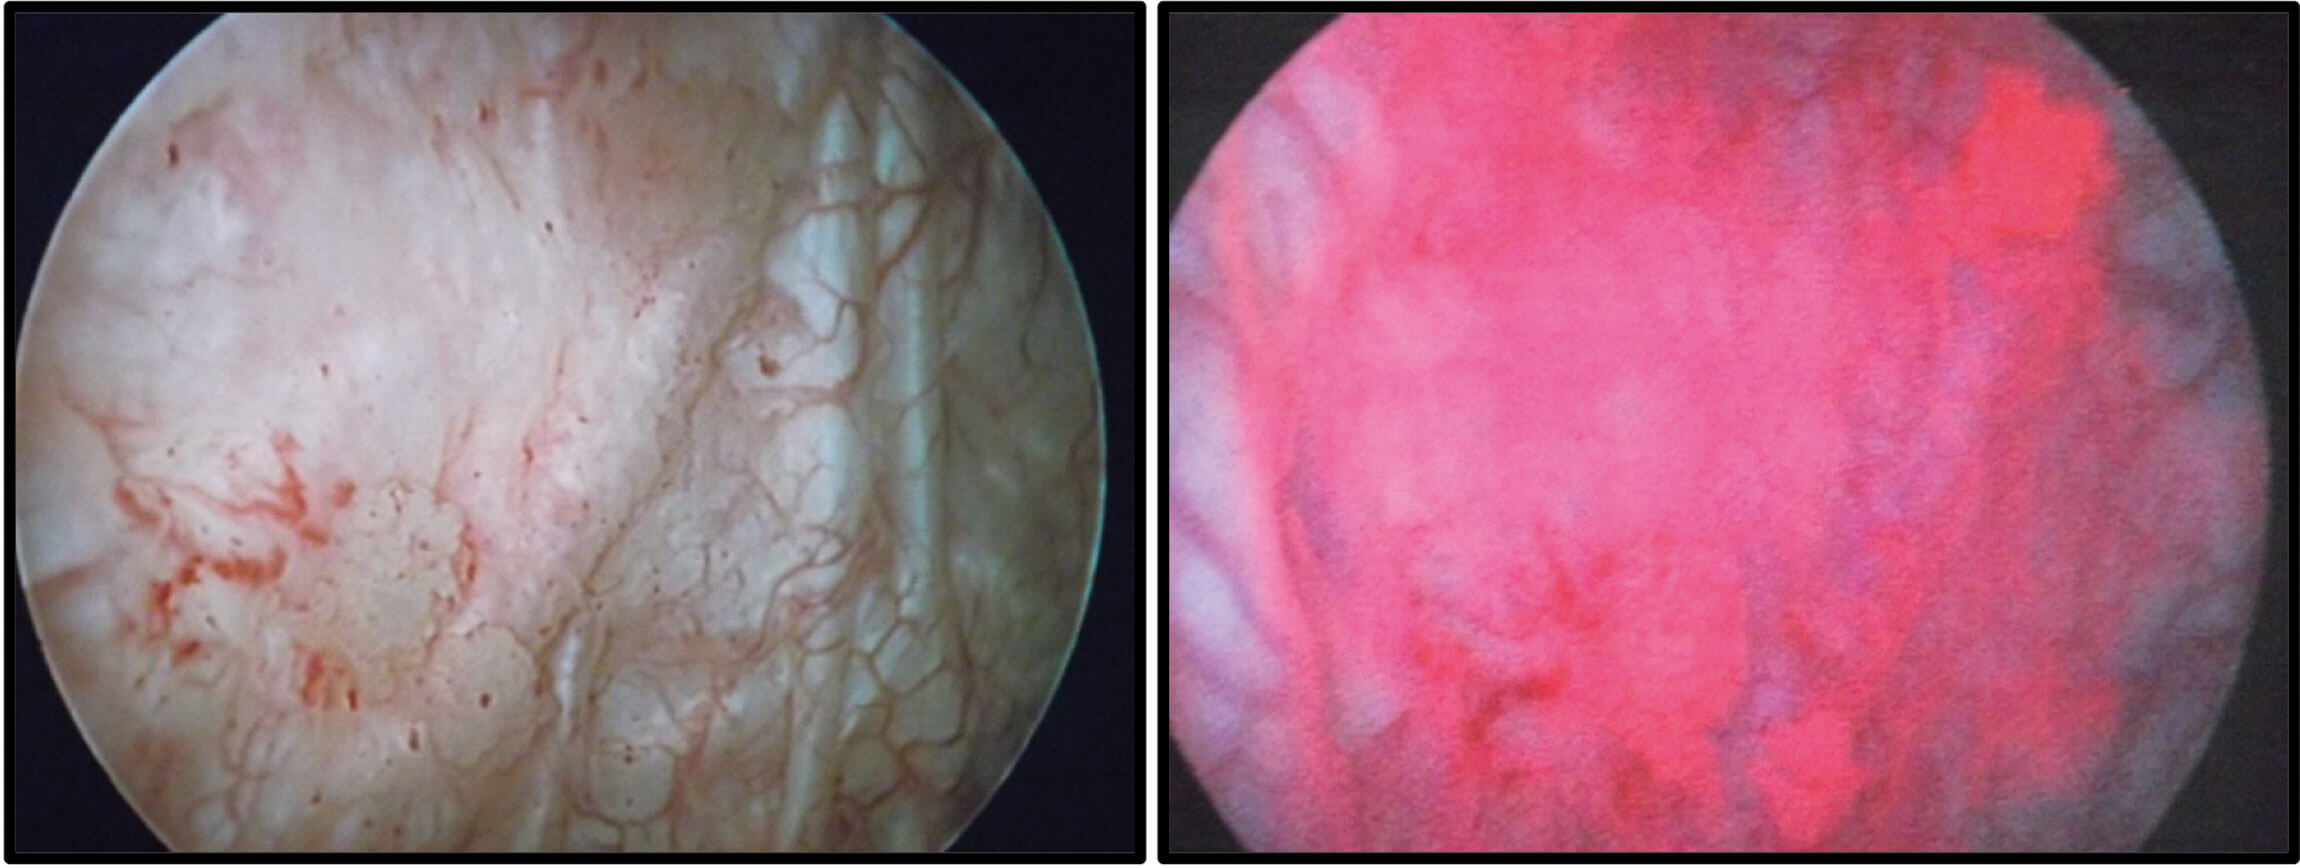

Figure 2: Cystoscopy of a patient diagnosed with CIS. The right shows the red appearance of CIS with PDD,

whilst the left shows the difficulty of detection with WLC (images courtesy of Miss J Cresswell).

Photodynamic diagnosis (PDD) involves instillation of hexaminolevulinate (Hexvix®) into the bladder. Tumour cells have a higher uptake than the surrounding mucosa, and the photoactive porphyrin emits a red fluorescence when viewed under blue light. Figure 2 demonstrates the stark difference in the appearance of CIS when using PDD versus WLC. Many studies have demonstrated the superior detection rate of cancer with PDD, however, a recent UK randomised controlled trial (PHOTO) of WLC and transurethral resection of bladder tumour (TURBT) versus PDD and TURBT, failed to show improved oncological or economic benefit of PDD [4,5].